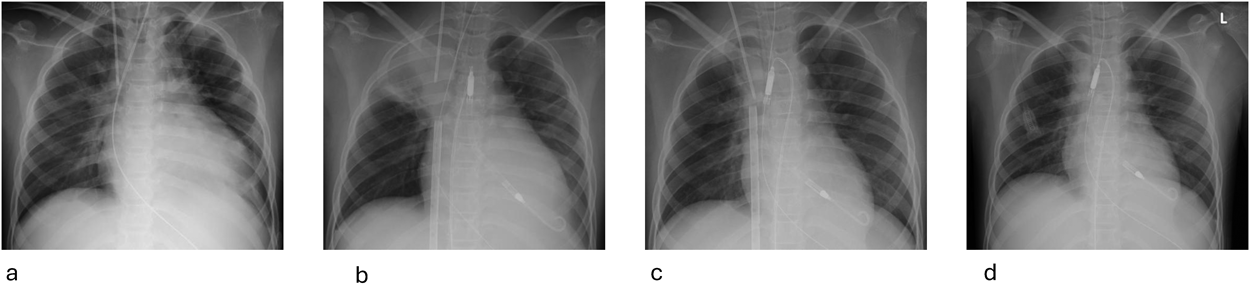

Impella®循環補助用心内留置型ポンプカテーテル(Impella® CP)と静動脈型体外式膜型人工肺により劇症型心筋炎の左室unloadingが著効した12歳男子例—体格の小さい患者における管理上の注意点A 12-year-old male case of successful left ventricular unloading utilizing Impella CP® and veno-arterial extracorporeal membrane oxygenation due to fulminant myocarditis—Precautions for management in patients with small stature